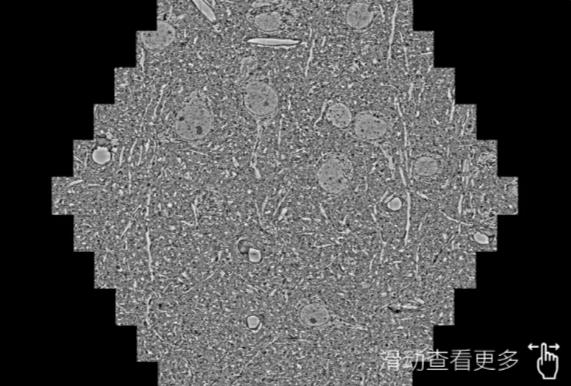

鼠脑切片。左图使用海东蔡司海东扫描电镜MultiSEM706对165μmx143pm面积区域成像,耗时仅需1.5秒。右图为鼠脑切片中30μm区域放大效果。样品由芝加哥大学B.Kasthuri提供。

使用蔡司高速海东扫描电镜MultiSEM对1mm²人脑皮层组织进行高分辨成像,并对其中的各种细胞结构进行三维重构分析。左图展示了2x3mm²组织平面中锥体神经元的三维重构效果。右图显示了局部体积神经元三维重构。图像由哈佛大学chtman实验室提供,渲染图由D. Berger 制作。